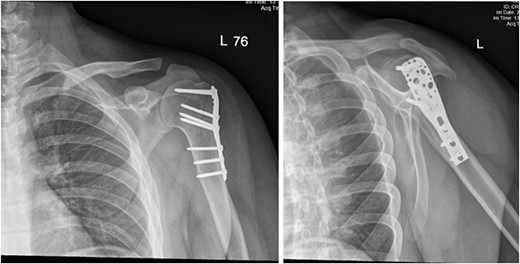

Upon arrival the patient underwent exploratory laparotomy followed by irrigation and debridement of both femur and humerus and application of external fixators (Fig. 2). The patient was admitted to the intensive care unit (ICU). Two days later, the patient underwent open reduction and internal fixation of both proximal and distal humerus (Fig. 3).

Anteroposterior (AP) view of the left humerus and elbow after Ex-fix application.